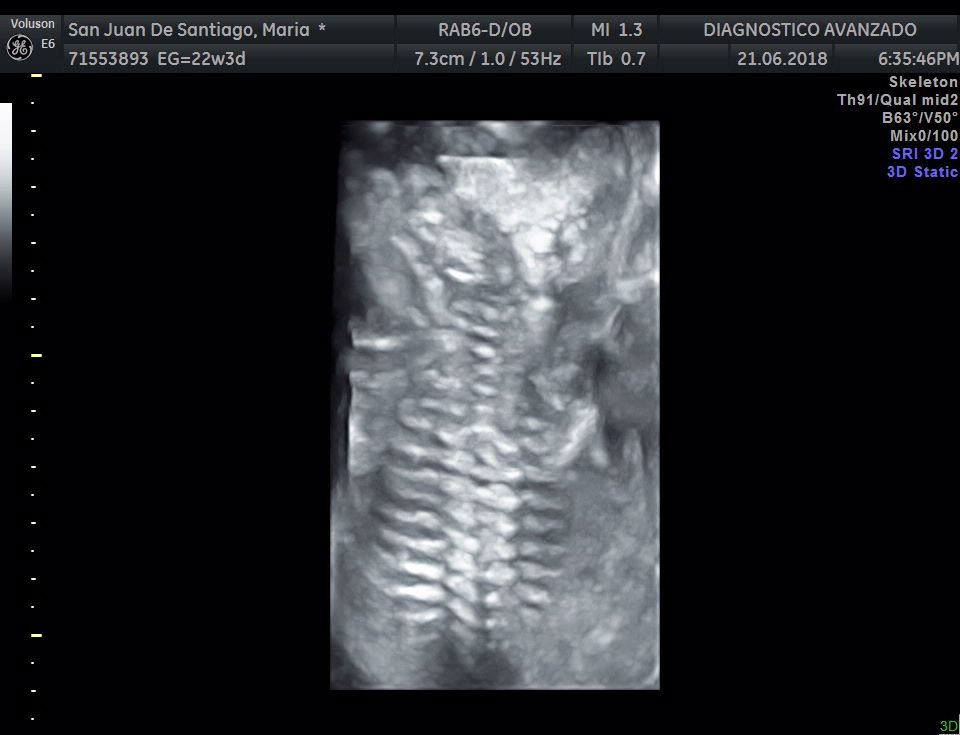

¡Hola a todos! Hoy hemos ido a hacer la tradicional ecografía 3D de la niña, os dejamos todo el material (aunque es un poco demasiado).